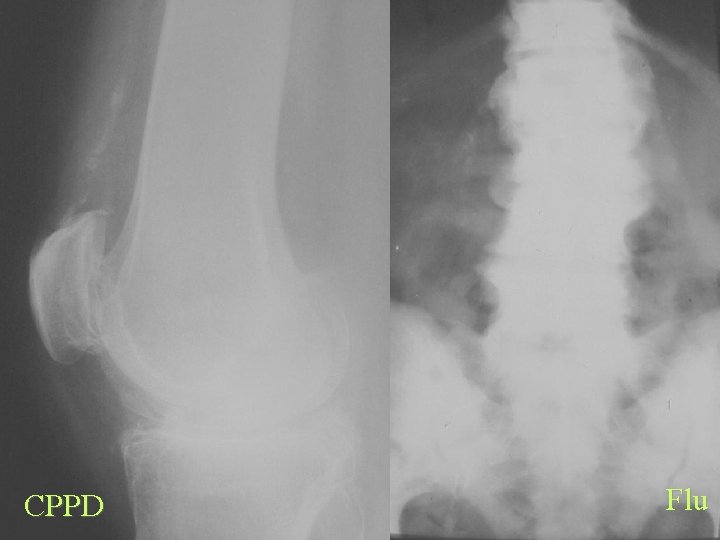

CPPD Flu

Calcification By site Tendons and Bursa CPPD • Linear • Articular • Achilles, Quads, Tri • Ass. arthritis MCPCDD • • HADD Rounded Amorphous Tendons and Bursa Rotator cuff